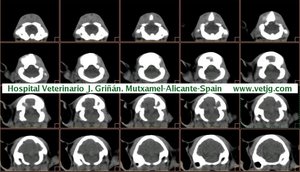

imágenes de TC en el gato | |||||||||||